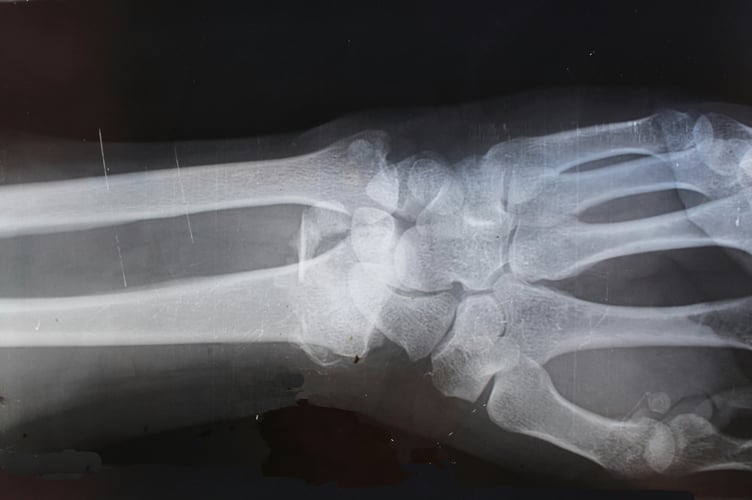

Funded by Welsh Government, the new equipment will produce faster, clearer images than ever before, helping to improve diagnostics for the people of Powys.

In addition to the improved quality and speed, the new X-ray machines use a lower dose of radiation than the existing machines, which in turn reduces the radiation exposure for patients.